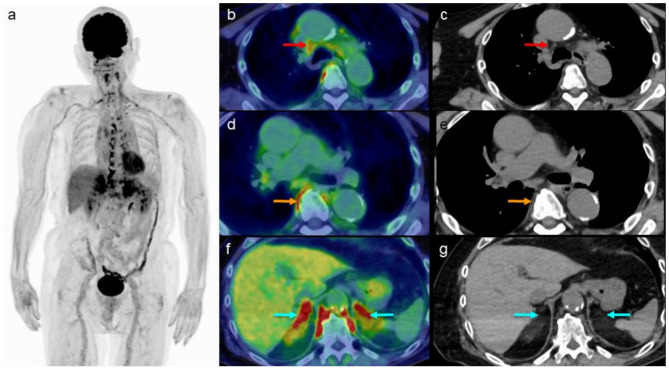

Background: Brown adipose tissues (BAT) are highly vascularized, mitochondria-rich tissues involved in thermogenesis. Physiological [18F]fluorodeoxyglucose ([18F]FDG) uptake in BAT can be influenced by several factors, including the use of medications that act on β-adrenergic receptors. Recently, increased [18F]FDG BAT uptake has been observed in elderly patients (≥ 60 years old) receiving β3-adrenergic receptor agonists. With the increasing use of β3-adrenergic receptor agonists for managing overactive bladder, there is limited understanding of their potential association with increased [18F]FDG BAT uptake. This study retrospectively investigated whether treatment with β3-adrenergic receptor agonists is associated with increased [18F]FDG BAT uptake among elderly patients. [18F]FDG positron emission tomography (PET) images were analyzed visually and through SUVmax measurements across eight predefined regions of interest (ROI): cervical, periclavicular, axillary, mediastinal, paravertebral, paraabdominal aortic, perirenal, and perisplenic regions. Patients' medication history and clinical records were reviewed to assess β3-adrenergic receptor agonist use relative to their [18F]FDG PET study.

Results: Forty-four elderly patients, each with a single [18F]FDG PET scan, were included in the analysis. Among the eight ROIs, the perirenal region showed a statistically significant increase in [18F]FDG BAT uptake in patients receiving β3-adrenergic receptor agonists compared with those not receiving, based on both visual analysis (p < 0.001) and SUVmax measurements (p = 0.030). All patients receiving β3-adrenergic receptor agonists demonstrated increased [18F]FDG BAT uptake in the paravertebral region.

Conclusion: In patients aged ≥ 60 years, β3-adrenergic receptor agonist therapy appears to be associated with increased [18F]FDG BAT uptake, particularly in the perirenal area.